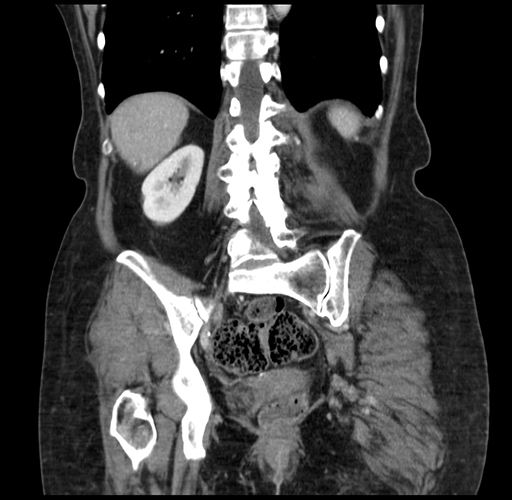

Pre-Chemo: Coronal Venous

Coronal Venous